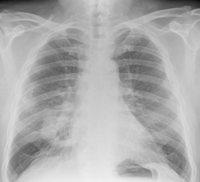

Nueva diana frente a las metástasis hepáticas en pacientes con cáncer de pulmón